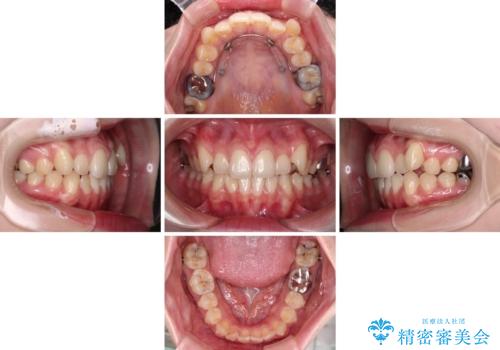

上顎の八重歯改善にインビザラインでは時間のかかってしまう可能性があり、更には口元が治療前よりも突出してしまう可能性があったため、補助装置により八重歯を事前に引き込んでおくことで、インビザラインによる治療をスムーズに行えるように計画しました。

補助装置を使用したことで、口元が突出することもなく、スムーズに仕上げることができました。